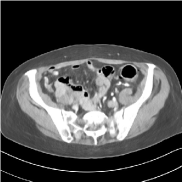

This special case of SUPER corresponds to the case where SUPER excludes the unsupervised regularizer, while only involves the data-fidelity and a supervised regularizer in the MBIR cost, i.e., β=0𝛽0\beta=0 and μ0𝜇0\mu\neq 0. In this case, the proposed SUPER model is similar to a generalized block coordinate descent-based network by replacing a simple denoising autoencoder [28, 29, 30] with a general CNN that forms our supervised regularizer. This SUPER is also similar to the plug-and-play ADMM-Net method except that the inputs to each supervised network are the preceding reconstructions, while plug-and-play ADMM-Net updates inputs to the network (denoiser) based on auxiliary variables in the ADMM algorithm. Here, we used μ=1×106𝜇1superscript106\mu=1\times 10^{6}, which worked well for the plug-and-play ADMM-Net method, for this special case of SUPER. Fig. 7 shows a comparison between plug-and-play ADMM-Net, SUPER without unsupervised regularizers (in both training and testing), and the full SUPER version with ULTRA regularization (β=5×103𝛽5superscript103\beta=5\times 10^{3}, μ=5×105𝜇5superscript105\mu=5\times 10^{5}). All these methods used WavResNet as their denoisers/supervised networks. In this example, SUPER with only a supervised regularizer (SUPER-WRN-β=0𝛽0\beta=0) outperforms the plug-and-play ADMM-Net (ADMM-Net (WRN)) by 1.6 HU RMSE and provides sharper image details. Comparing SUPER-WRN-β=0𝛽0\beta=0 and the full SUPER-WRN-ULTRA scheme, we observe that the latter provides a lower RMSE and higher contrast image features than the former that excludes the unsupervised component. This again shows the effect of the unsupervised ULTRA model (in capturing local image details better with a union of learned transforms) in the SUPER scheme.

Refer to captionADMM-Net (WRN)RMSE = 32.90 HURefer to captionADMM-Net (WRN)RMSE = 32.90 HU

Refer to captionSUPER-WRN-β=0𝛽0\beta=0RMSE = 31.32 HURefer to captionSUPER-WRN-β=0𝛽0\beta=0RMSE = 31.32 HU

Refer to caption SUPER-WRN-ULTRARMSE = 29.74 HURefer to caption SUPER-WRN-ULTRARMSE = 29.74 HU

Refer to caption ReferenceRefer to caption Reference

Figure 7: Reconstructed images of L192 slice 150 with WavResNet plugged ADMM-Net, SUPER-WRN-β=0𝛽0\beta=0 (both training and testing), and SUPER-WRN-ULTRA (β=5×103𝛽5superscript103\beta=5\times 10^{3} in both training and testing), respectively, shown with the reference image.